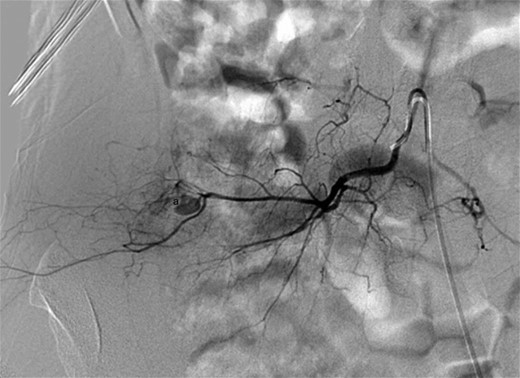

Examination on admission revealed an actively bleeding 2-cm wide stab wound in the right lumbar paraspinal region. A contrast-enhanced CT of the pelvis showed an enhancing lesion consistent with a pseudoaneurysm extending from a branch of a right lumbar artery (Figs 1 and 2). The patient was transferred to the interventional radiology suite where angiography confirmed the diagnosis (Fig. 3). The pseudoaneurysm was then successfully embolized using platinum microcoils (Fig. 4), which were positioned in the lumbar artery, proximal and distal to the origin of the pseudoaneurysm. The patient tolerated the procedure well and was discharged the following day without any further complication.

Digital subtraction angiography showing a small pseudoaneurysm originating from the peripheral aspect of the distal right lumbar artery (a).